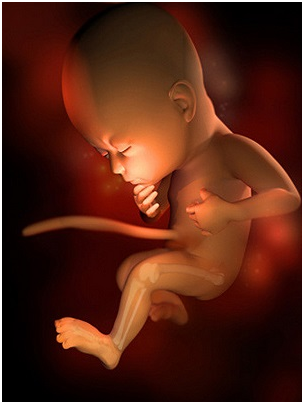

怀孕第10周在怀孕前,你的子宫大概和小香梨一样大,但现在已经长到一个大橙子那么大了。这段时间...

怀孕第10周在怀孕前,你的子宫大概和小香梨一样大,但现在已经长到一个大橙子那么大了。这段时间... -